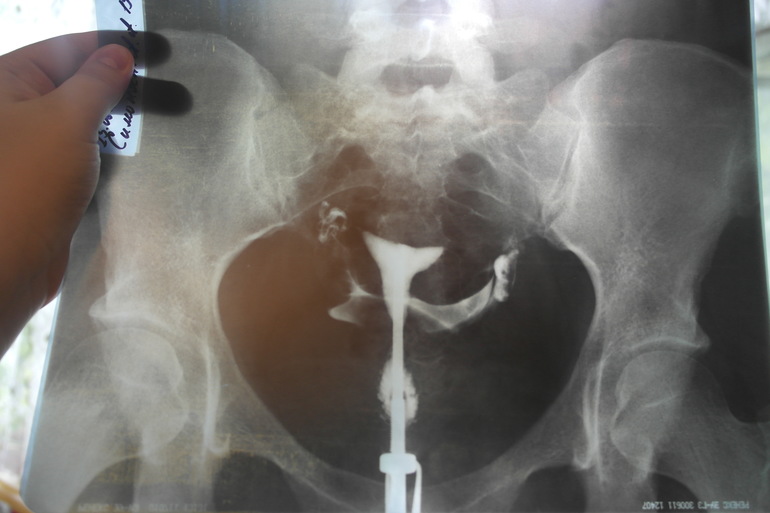

Результаты ГСГ

ГСГ, ЭХО, МСГ, ФертилоскопияСохраняю скорее для себя)))) Но я все равно ничего не пойму на этих снимках) ни где трубы, ни где яичники, хотя много фото пересмотрела в инете, везде было понятно(((((

1 фото без раствора

2 фото 3 минуты с раствором

3 фото 7 минут с раствором

заключение